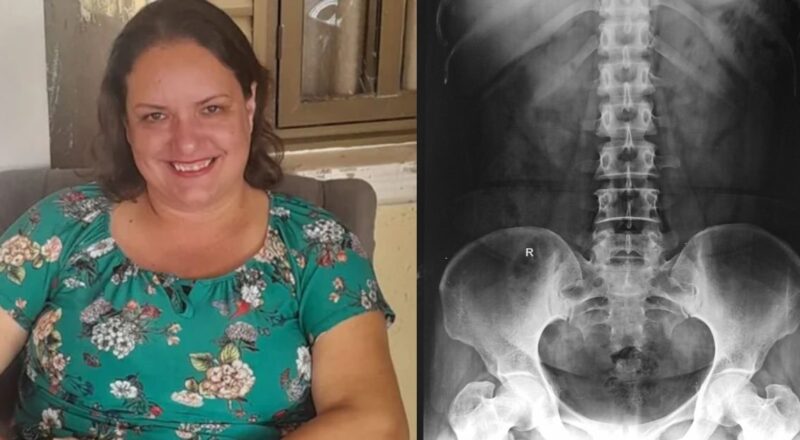

Grávida descobre câncer silencioso após sangramento durante exame de rotina do pré-natal

O que deveria ser apenas o início de mais uma gestação tranquila acabou se transformando em um dos momentos mais desafiadores da vida de uma […]